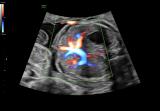

东芝将携尖端科技亮相2020进博会 3D超声技术加速行业转型升级

本届展会,东芝将以“点亮崭新未来”为主题,为商业用户带来纯氢燃料电池发电系统等全球尖端科技产品,以及清洁能源、可再生能源、智能楼宇、3D超声波检测装置和重离子肿瘤治疗等解决方案,通过沉浸式及交互式观感的特殊体验方式,展现丰富的产品与技术,助力产业创新和社会发展。 2020-10-22 仪器仪表